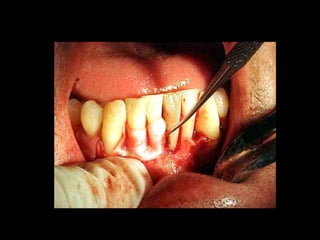

La periodontitis, denominada comúnmente piorrea, es una enfermedad que

inicialmente puede cursar con gingivitis, para luego proseguir con una pérdida de

inserción colágena, recesión gingival, e incluso la pérdida de hueso, en el caso de

no ser tratada, dejar sin soporte óseo al diente. La pérdida de dicho soporte

implica la pérdida irreparable del diente mismo.

De etiología bacteriana que afecta al periodonto (el tejido de sostén de los dientes,

constituido por la encía, el hueso alveolar, el cemento radicular y el ligamento

periodontal) se manifiesta más comúnmente en adultos mayores de 35 años, pero

puede iniciarse en edades más tempranas.

Periodontitis